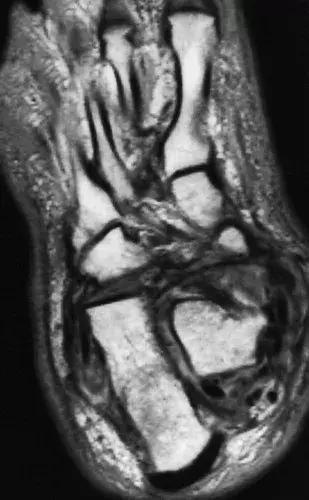

图20: 65岁糖尿病男性的神经性关节病。 轴向质子密度加权自旋回波(2,500/45)(a)和矢状面反转恢复(4,000/60/160 [反转时间msec])(b)MR图像显示内侧距骨脱位和积液。 踝部和足部周围存在广泛的软组织水肿。 由于缺乏交感神经血管收缩,在神经性骨关节病中常见软组织水肿。